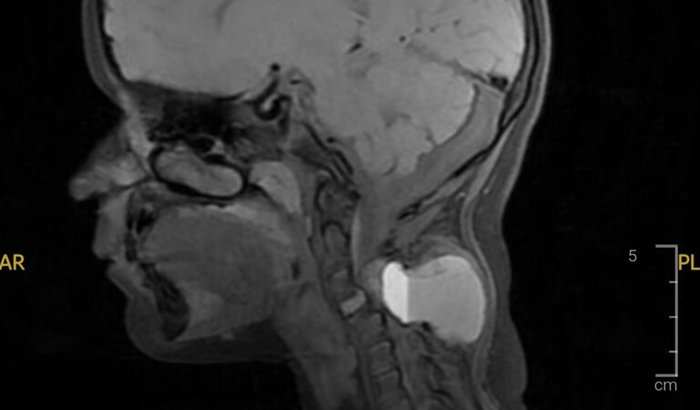

Recentemente, ela foi diagnosticada com um cisto ósseo aneurismatico na região cervical, que está comprimido nervos, a medula e afetando os ossos dessa área. Esse quadro requer uma cirurgia importante para a remoção do cisto e descompressão da medula, além de diversos exames, biópsias, medicamentos e também o uso de colares cervicais especial no pós-operatório.